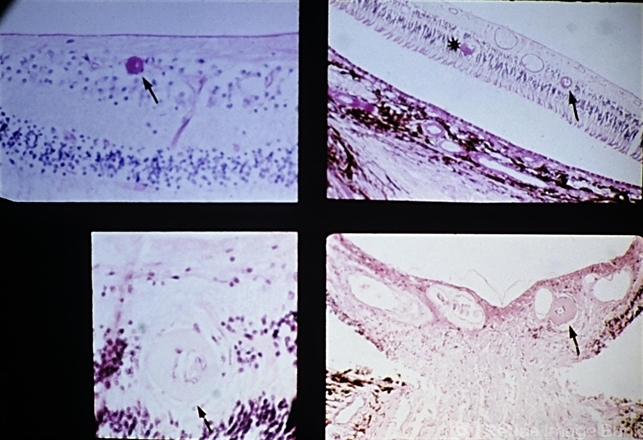

- malignant hypertension, retinal arteriole, fibrinoid, retinal exudates, papilledema

- Malignant hypertension with retinal arterioles that are thickened and have fibrinoid necrosis (arrows). Retinal exudates (asterisk) and papilledema are also present. Papilledema is evidenced by fullness of the optic nerve head and peripapillary crowding of the retina (lower right).